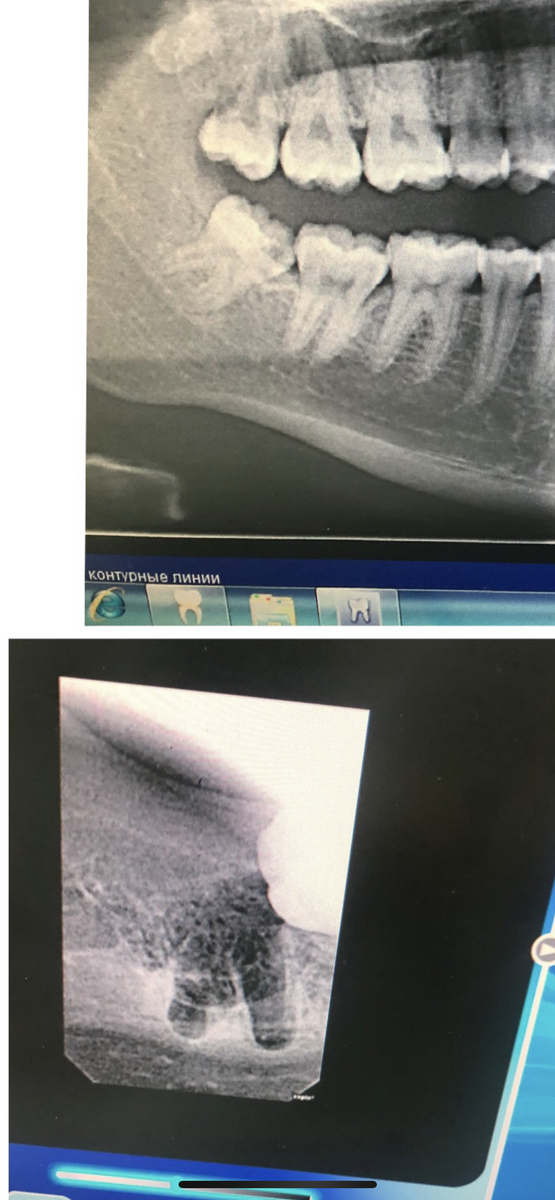

Как правило , эти зубы прорезываются неправильно. Могут воздействовать на предстоящие зубы и вызывать кариес корня или вообще толкать весь зубной ряд .

По расположение в кости их подразделяют на дистопированные

(когда они прорезались неправильно ) и ретенированные

(когда они находятся в неправильном положении уже в кости)